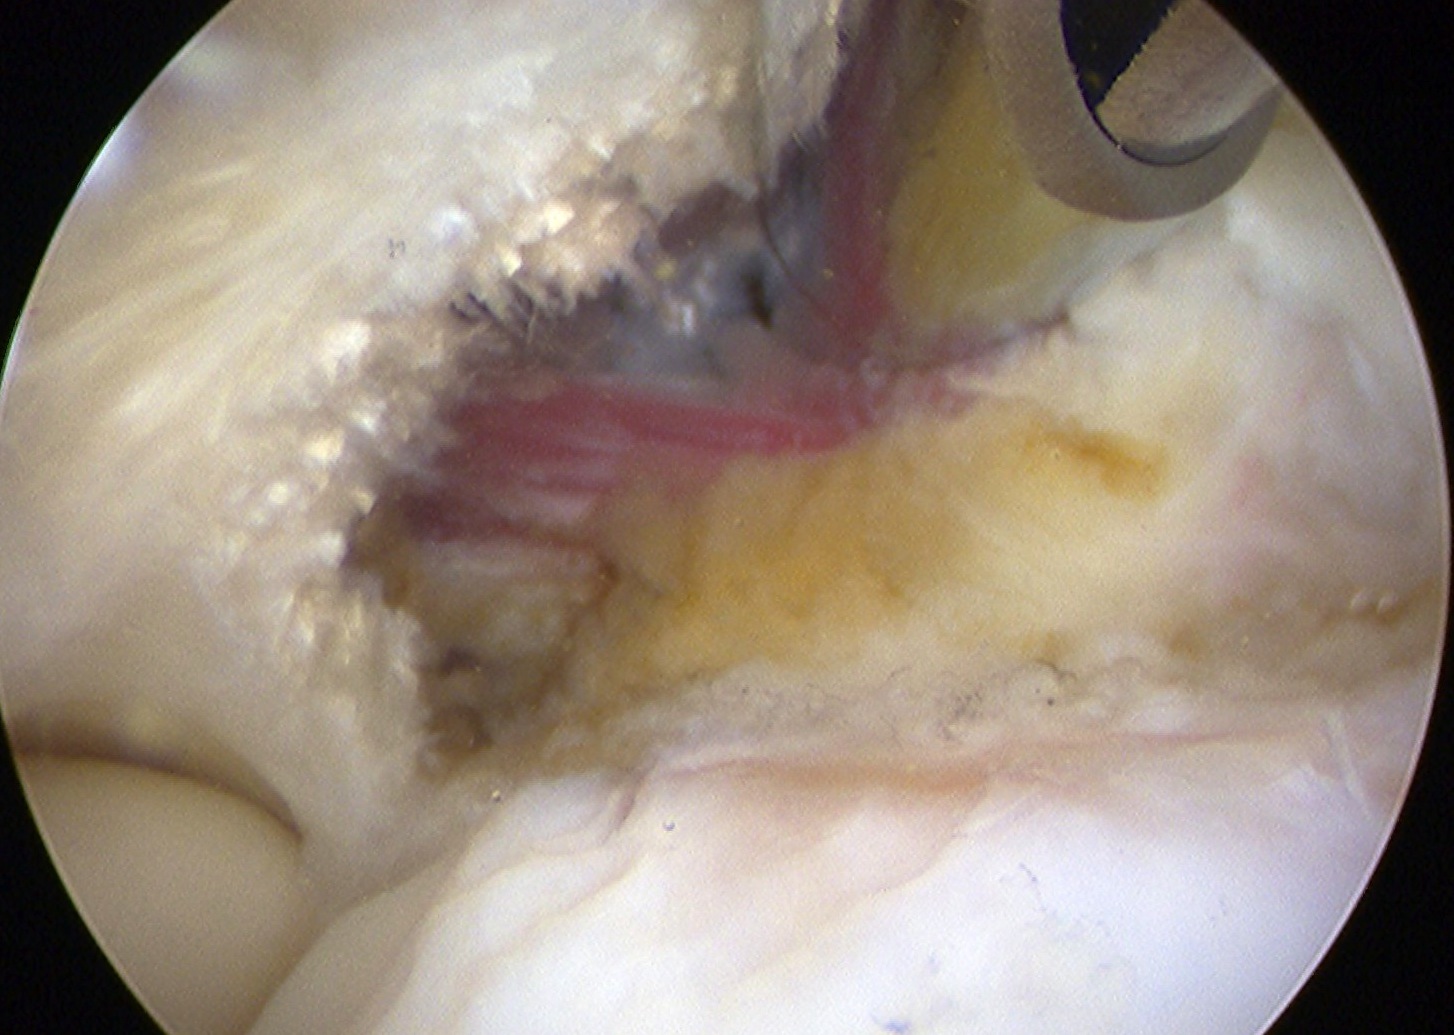

Arthroscopic tennis elbow release

Technique

Enter radiocapitellar joint

- release capsule

- release ECRB